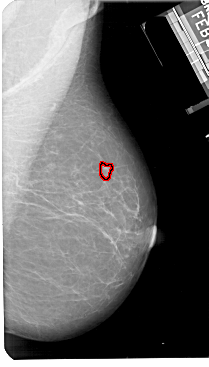

A_1871_1.RIGHT_CC

RIGHT_CC LINES 5371 PIXELS_PER_LINE 2881 BITS_PER_PIXEL 12 RESOLUTION 43.5 OVERLAY

FILE: A_1871_1.RIGHT_CC.OVERLAY

TOTAL_ABNORMALITIES 1

ABNORMALITY 1

LESION_TYPE MASS SHAPE IRREGULAR MARGINS ILL_DEFINED

ASSESSMENT 4

SUBTLETY 1

PATHOLOGY MALIGNANT

TOTAL_OUTLINES 1

BOUNDARY